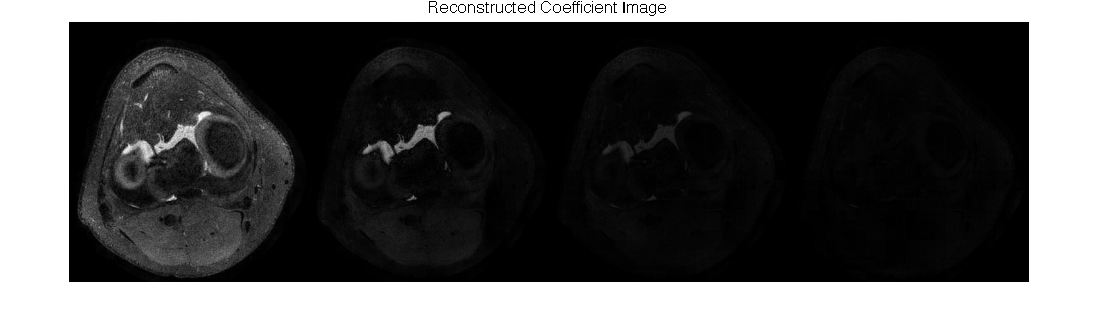

figure(2);

imshow(abs(reshape(alpha, ny, [])), []);

ftitle('Reconstructed Coefficient Images');